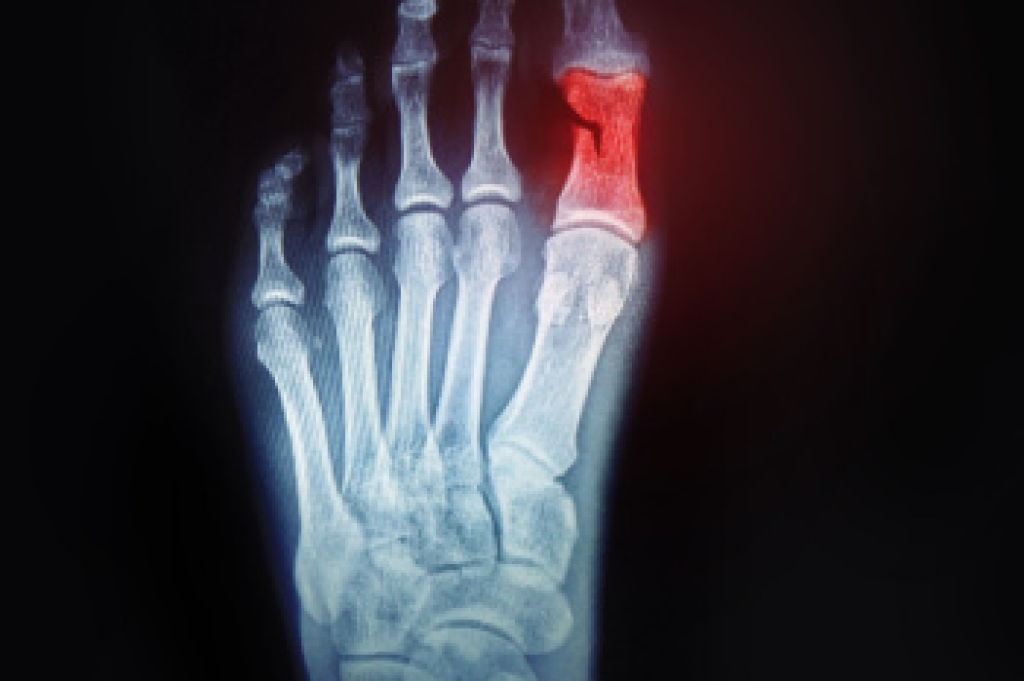

A broken toe occurs when one of the bones in the toe cracks due to trauma or repeated stress. Common causes include stubbing the toe, dropping a heavy object on the foot, or overuse in activities like running. Symptoms include swelling, bruising, pain, difficulty walking, or visible deformity. Risk factors include poor footwear, reduced bone density, and high-impact activities. A podiatrist can confirm the diagnosis through a physical exam and imaging, then recommend appropriate care such as splinting, immobilization, or, in some cases, surgery. If you suspect a broken toe, it is suggested that you make an immediate appointment with a podiatrist to receive expert treatment and prevent long-term complications.

Although most people try to avoid foot trauma such as banging, stubbing, or dropping heavy objects on their feet, the unfortunate fact is that it is a common occurrence. Given the fact that toes are positioned in front of the feet, they typically sustain the brunt of such trauma. When trauma occurs to a toe, the result can be a painful break (fracture).

Severe toe fractures may be treated with a splint, cast, and in some cases, minor surgery. Due to its position and the pressure it endures with daily activity, future complications can occur if the big toe is not properly treated.